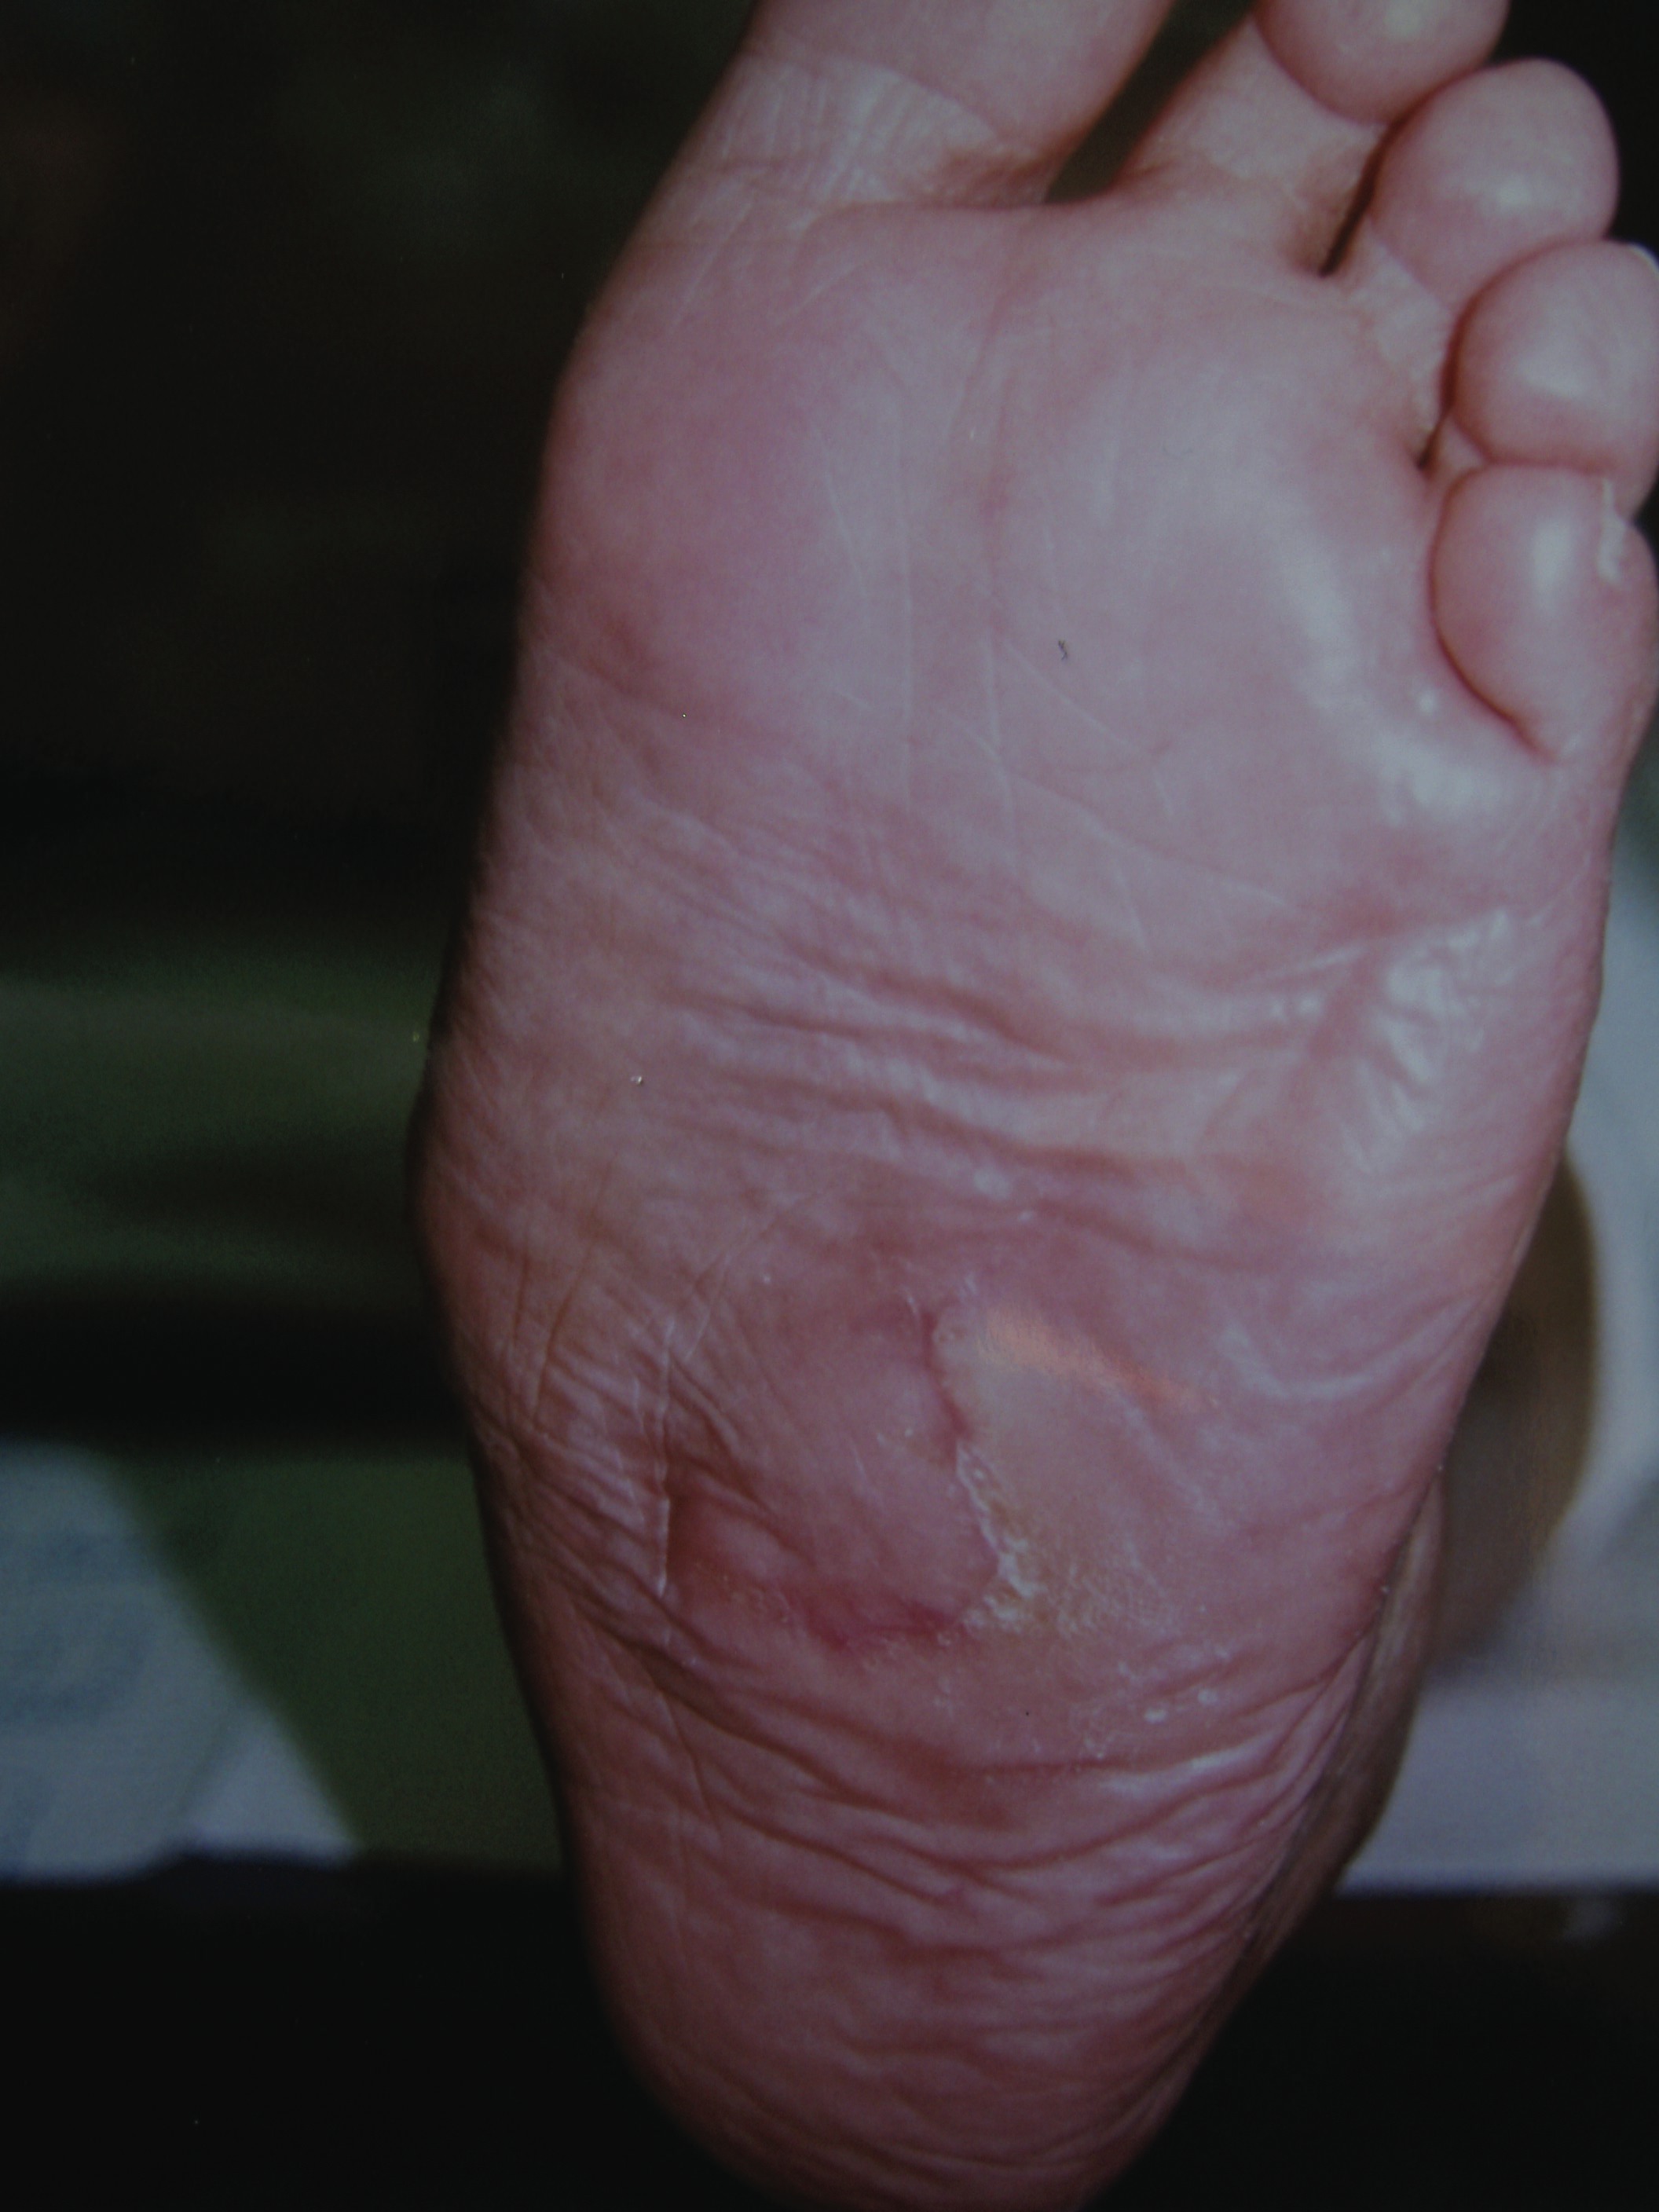

Local flaps are very useful in the foot for covering defects on weightbearing surfaces where a skin graft would most likely fail. Researchers have described many different flaps, all of which have various pros and cons.2 There are many factors surgeons must consider in order to choose an appropriate local flap. These factors include the location, size, shape and depth of the defect as well as the amount, type and mobility of the surrounding skin. For example, the skin on the plantar surface of the foot adheres tightly to the underlying fascia, making rotation of the flap more difficult if the flap is poorly designed. Preoperative planning is essential to preventing excessive tension across the flap. Excessive tension can compromise the vascularity of the flap or lead to wound dehiscence. Trying to determine how much tension is excessive can be difficult since the amount of tension a flap may tolerate varies from patient to patient and depends upon multiple factors. As a general rule of thumb, if a flap can hold its new position without breaking a 4-0 monofilament nylon suture, the tension is probably not excessive. When one rotates a flap, blanching of the flap may occur. The first step I take intraoperatively in this situation is to raise the head of the table and apply a warm saline compress. The blanching may be due to vasospasm and may subside after several minutes. If the flap fails to “pink up,” there may indeed be too much tension across the flap and several techniques can relieve this tension. Removing a few of the sutures may be enough to allow the flap to perfuse. If this fails, one should remove all the sutures and allow the flap to return to its original position. If the flap fails to perfuse when it is back in its original position, the vascularity to the flap may have been compromised and this is a concern. In this situation, I would leave the flap in its original position and secure it in place. The vascularity of the flap may increase over the next few days by a process referred to as a delay phenomenon. This process begins when the surgeon raises the flap and cuts vessels on three sides of the flap. The blood flow through the remaining side will increase its capacity over the next few days. This may allow the patient to return to the operating room and one can make another attempt to rotate the flap. If one places the flap in its original position and it does perfuse, then excessive tension is the problem. The surgeon can then perform undermining of the tissue around the defect, taking care to avoid undermining the flap base. Undermining the surrounding tissue instead of the flap base will cause the least amount of disruption of the blood supply to the flap. One should proceed to rotate the flap once again. If it blanches again, there is still too much tension. Surgeons may attempt to undermine the base of the flap but keep in mind that doing so can compromise the vascularity to the flap. Accordingly, one should do this with great caution and with the least amount of undermining necessary to decrease the tension. Finally, make a back cut at the base of the flap where one will find most of the tension. Use this technique with caution since it will narrow the base of the flap and reduce the inflow of blood. If blood flow into the flap continues to be restricted, place the flap back in its original position and bring the patient back to the operating room after the flap has had a chance to increase its vascularity.

Dog ears are an inevitable consequence when tissue rotates around an axis. Excessive dog ears occur when a flap rotates around a large angle or as a result of a poorly designed flap. The surgeon does not need to address most dog ears since they will often flatten in time. Addressing a dog ear at the time of the original surgery can further compromise the flap so one should exercise great caution. If necessary, surgeons can deal with dog ears in the future once the flap is fully revascularized.3 In a similar fashion, involutions of tissue can occur when tissue rotates. Involutions can occasionally be problematic and lead to callus formation and ulceration. In these cases, one can address the excess tissue in a manner similar to dog ears. Avoid removing excessive tissue from the plantar surface of the foot since this is very unique tissue and it is paramount to preserve as much of it as possible. One can accomplish this by choosing the correct flap for the particular defect. Surgeons should keep in mind that recurrent ulcers are common in the neuropathic foot and any excess tissue may be useful in future procedures. When choosing a flap, one should also consider the possibility of needing to elevate and rotate a flap a second time for a recurrent ulceration. Some flaps are more amenable to this than others.